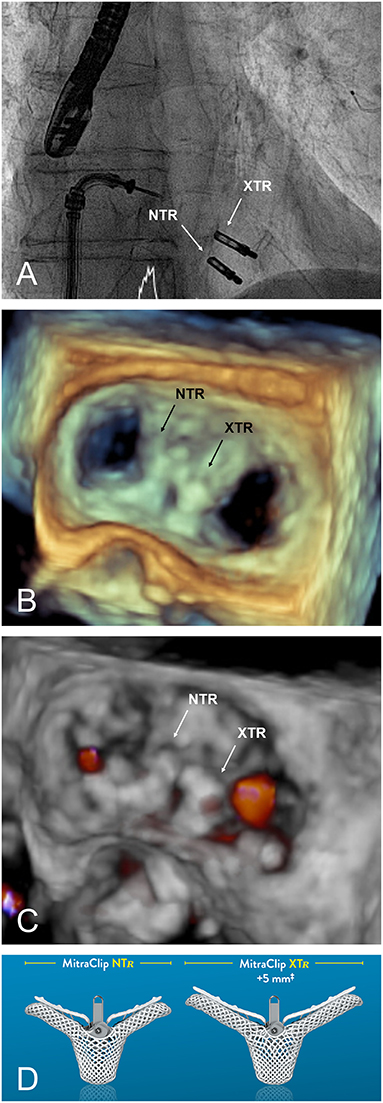

Both TTE and TEE should be reviewed by the Heart Team to confirm eligibility and intraprocedural approach to MV repair. Agreement should be made as to the precise location for device placement, number of device, and treatment strategies, particularly with more challenging anatomy as defined in Table 1.